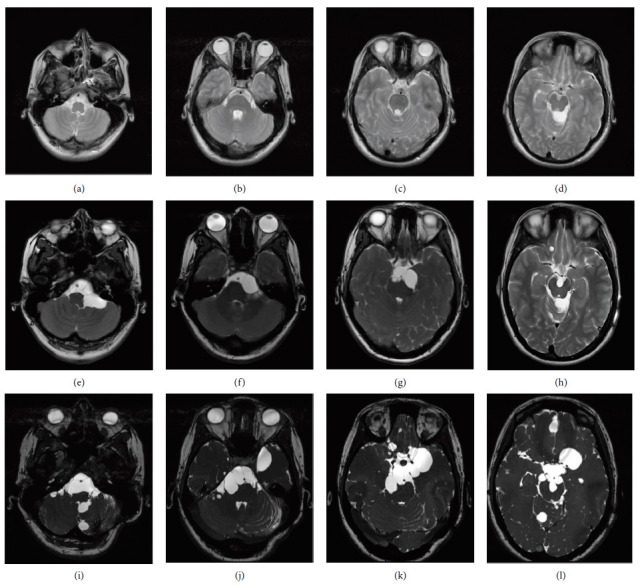

Neurenteric cysts (NECs) are rare congenital, benign lesions of the central nervous system (CNS), predominantly located within the spinal cord. However, they may also occur less frequently within the brainstem, fourth ventricle, or cerebellopontine angle (CPA). Originating from anomalous interactions between embryonic layers, NECs are recognized for their potential to compress adjacent structures. We report a unique case of disseminated NECs exhibiting few to absent symptoms, which represents an unusual presentation of this disease, with only six similar reports in the literature. A 22-year-old female presented to our institute with chronic headaches resistant to nonsteroidal anti-inflammatory drugs (NSAIDs). Initially treated for intracranial hypertension (ICH) secondary to a cyst in the quadrigeminal cistern at the age of 17 via neuroendoscopic surgery and subsequent ventriculoperitoneal shunting, she experienced transient relief. However, follow-up at 22 years of age revealed multiple cysts in the basal and spinal cisterns, with MRI findings suggestive of neurocysticercosis. Despite treatment with albendazole and corticosteroids, subsequent MRIs showed no change in the size or number of the cysts. Six years later, symptoms had worsened, previously identified cysts had grown, and the detection of new cysts prompted surgical intervention. Histopathological examination confirmed the presence of NECs. This case highlights the diagnostic challenges posed by NECs, especially in regions endemic for neurocysticercosis, where clinical and radiological findings may initially suggest this condition. It underscores the importance of considering NECs in the differential diagnosis of cystic lesions in the CNS, even in the absence of typical symptoms of spinal cord compression. The recurrence and spread of NECs post-treatment demand a comprehensive management approach, encompassing surgical intervention and close monitoring.